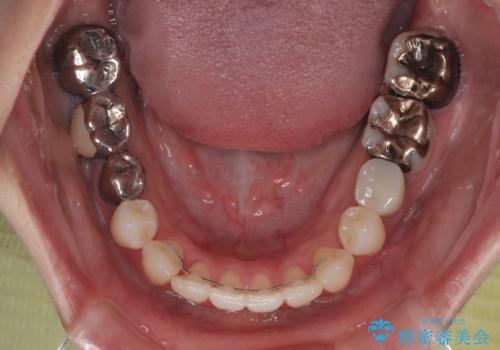

- 上下前歯のデコボコとクロスバイトを気にして来院された患者様です。

治療済みの処置歯が多いため、インビザラインを用いて矯正治療を行うこととしました。

下顎臼歯部にブリッジが装着されており、移動不可のため、IPR(歯と歯の間を削る)と歯列全体を拡大させることで、歯並びを整えていくこととしました。

インビザライン特有の奥歯の噛みにくさが治療後半に発現しましたが、無事に終了させることができました。